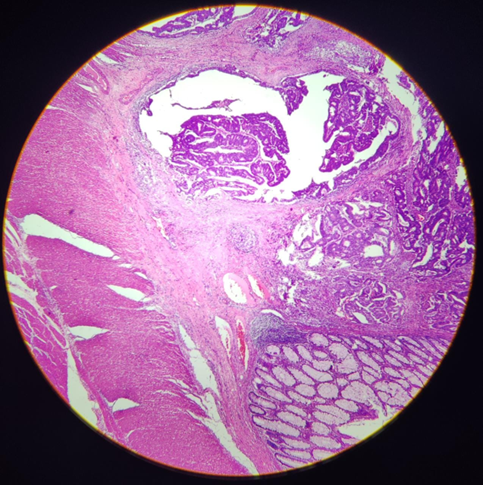

Órgão: Canal anal/Reto

Descrição: Fragmento de reto que se observa dilatação dos vasos associados com aumento do afluxo sanguíneo (congestão). Há vasos sanguíneos com trombos, com hemácias organizadas e presença de infiltrado inflamatório.

Diagnóstico: Trombo/congestão – hemorroida.